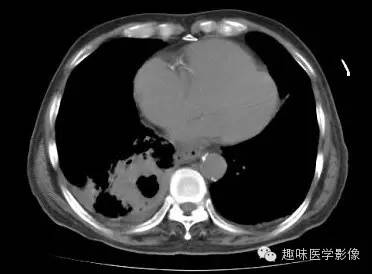

【病例】肺脓肿1例CT影像特点

男,71岁,发热待查。

双肺多发无壁低密度区,以右肺下叶底部为主。右肺下叶见大片不规则实变阴影伴多发空洞影,实变肺组织内见支气管气象,右肺下叶支气管局部显示不清。纵隔内见淋巴结。右侧胸腔内见积液影,邻近胸膜肥厚。主动脉、冠状动脉钙化。

右肺下叶肺脓肿、肺炎伴胸腔积液,肺气肿、肺大泡。

右胸廓变小,心影右移;右肺下叶多房性空洞,空洞内未见明显液平面,右下肺病变应该是下叶阻塞性肺炎,实变肺组织内见支气管气像,邻近胸膜增厚,并合并胸腔积液,支持肺脓肿。